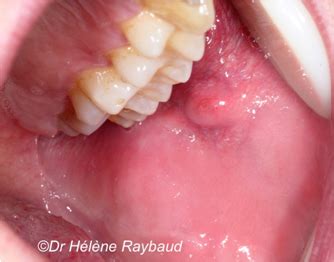

Cette maladie se manifeste surtout sur les lèvres, la face interne des joues et le palais Quand on a une affection bulleuse de la bouche, de petites bulles remplies de liquide (vésicules) se forment sur les muqueuses de la bouche Elle est source de gêne et d'inquiétude pour ceux qui en souffrent

bulles d'eau photo et image l'eau, gouttes, tourbillons, sujets Images. L'atteinte de la cavité buccale peut parfois être isolée Une cloque dans la bouche est une formation anormale qui se présente sous différentes formes et tailles, allant d'un petit renflement à une boule ressemblant à une cloque